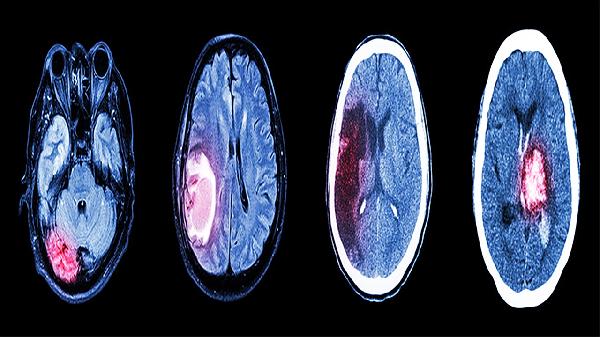

临床观察显示该药可能通过调节神经递质水平改善轻度认知障碍,但重度痴呆患者效果有限。用药期间需定期评估认知功能,若出现言语混乱、定向障碍等加重症状应及时就医排除脑血管病变等器质性疾病。